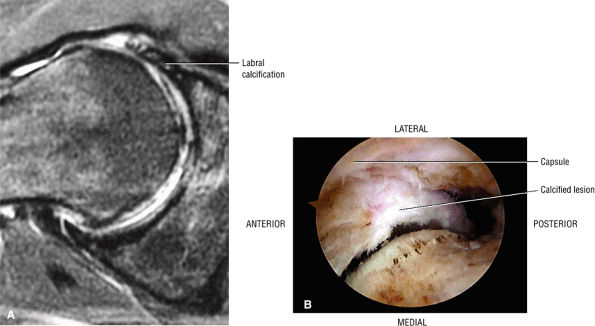

-

The superoposterior facet-gluteus medius tendon attachment (Fig. 3.148): the gluteus medius tendon attachment is posterior to the minimus attachment anteriorly and the muscular fibers of the medius attachment as viewed on sagittal images through the greater trochanter.

The posterior facet has no tendon attachments and is covered by the trochanteric bursa (see below).

![]() |

|